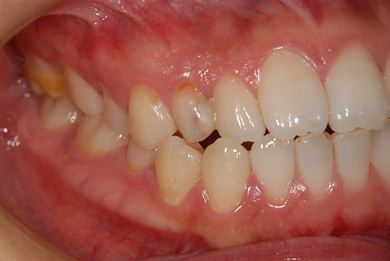

治療後

• 治療後